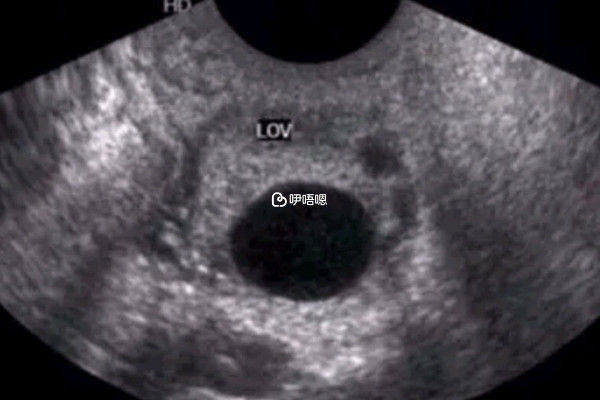

在試管嬰兒移植成功後患者需要定期到醫院進行B超檢查,主要是為了檢視胎兒的發育是否正常。一超一般是在移植成功後4周進行,主要的目的就是確定是否為宮內妊娠;二超則是在移植後38天做,主要是看胚胎在女性體內發育是否正常,排除早期胚胎停育的可能;三超是在懷孕11-13周的時候進行,檢查的主要目的就是進一步瞭解胎兒的健康狀況,是否存在畸形。